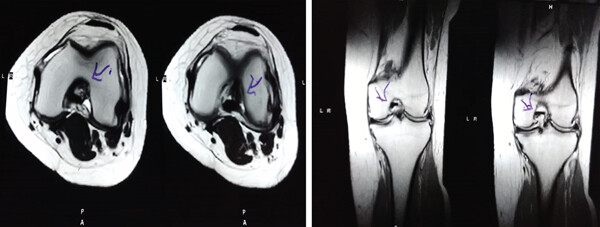

MRI:治療前后的MRI結果

治療前后的MRI結果

治療前 MRI 顯示內側和外側半月板后角 III 級撕裂。

治療后MRI檢查顯示內側和外側半月板后角撕裂有所改善?;颊甙Y狀改善,日常生活活動(dòng)能力增強。

結論:間充質(zhì)干細胞治療后,MRI檢查顯示內側和外側半月板后角撕裂有所改善 ,關(guān)節功能也有改善,未出現嚴重不良事件。可以達到干細胞治療半月板損傷短期療效的目標。